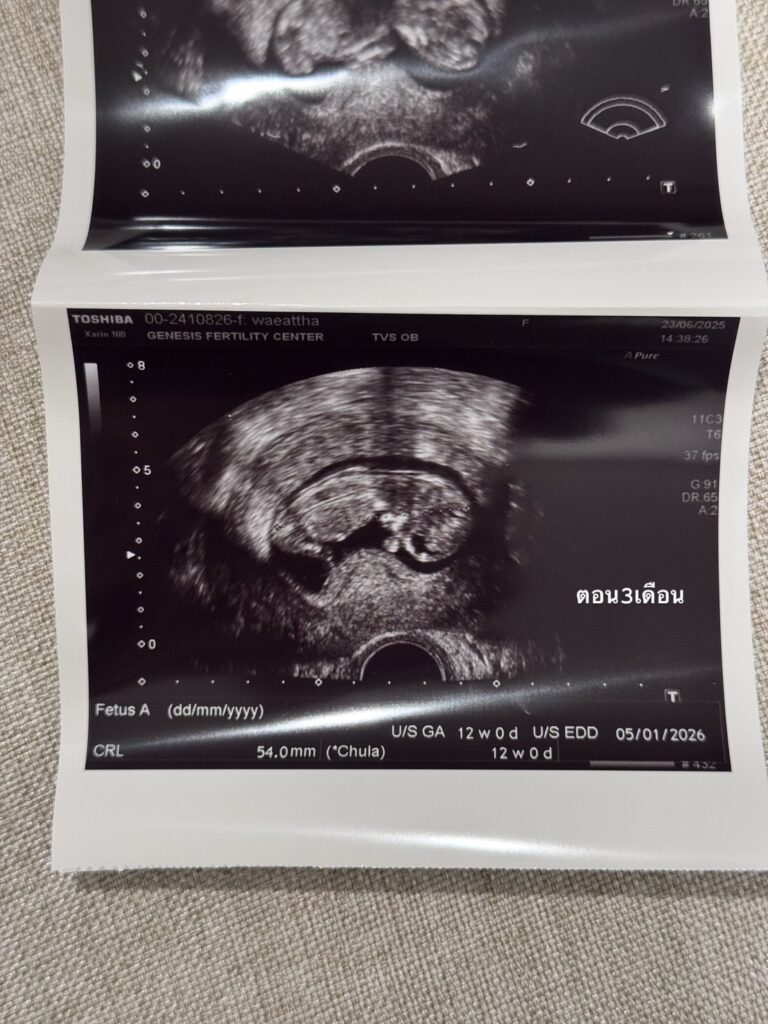

เป็นเรื่องราวดีๆ ให้แฟนๆ ได้เข้ามาร่วมแสดงความยินดีกันอย่างล้นหลาม สำหรับ “เนย วรัฐฐา” หลังจากที่ได้เข้ามาปรึกษากับทาง GFC (Genesis Fertility Center) หนึ่งในผู้นำด้านการรักษาผู้มีบุตรยาก จากความใส่ใจในความสำเร็จที่พร้อมเติมเต็มความฝันให้ทุกครอบครัวเสมอได้ช่วยสานฝันให้ “เนย วรัฐฐา” เป็นความจริง โดยล่าสุด ว่าที่คุณแม่เนยได้โพสต์รูปถือรูปอัลตร้าซาวด์ลูกคนแรกพร้อมข้อความที่อ่านแล้วต้องยิ้มตาม

@warutthaim ช่วงนี้หายๆไปเพราะว่าเนยมีน้องแล้ว 👼🏻 ในรูปคือประมาณ3เดือนตอนนี้ก็เกือบจะ4เดือนแล้ว ท้องป่องแล้ว😅 ต้องบอกว่าจะมีลูกคนนึงไม่ง่ายเลยเข้าใจว่าตัวเองแข็งแรงสุขภาพดีมาก ดูแลตัวเองมาอย่างดีมากๆ อาหารการกินคือคลีน ไม่ดื่ม ออกกำลังกายสม่ำเสมอ นอนไม่ดึก แต่ปรากฏว่า เนยบ้ายบายน้องไปถึง2 รอบ จนแปลกใจมากจริงๆเลยตัดสินใจไปหาคุณหมอมิงค์ ที่ @gfc.bangkok พอตรวจปรากฏว่า เนยละก็สามี มีโรคทางพันธุกรรมแฝงทั้งคู่ (เลยรู้สึกว่าก็โชคดีที่น้องบ้ายบายไปถึง2รอบเพราะถ้ารอดมาชีวิตก็คงลำบาก) โอกาสที่เด็กจะออกมาสมบูรณ์มีแค่25%เท่านั้น ซึ่ง%ที่เหลือคือเป็นโรคกับเป็นโรคแฝงแบบเนยที่ใช้ชีวิตปกติจนโตได้แต่เราก็จะมียีนที่ผิดปกติติดตัวส่งทอดไปสู่รุ่นอื่นๆได้ ซึ่งเนยเลือกที่จะให้ลูกสมบูรณ์100%เลยดีกว่า เลยเริ่มทำ ICIS กับทางคลีนิค ทั้งคัดโครโมโซม ตรวจคัดโรค และหลังใส่ตัวอ่อนก็ทำ NIFTY อีก (คือต้องเพอร์เฟคละมั้ย555) ต้องบอกว่าคุณหมอมิ้งค์ดูแลดีมากๆ ตั้งแต่วันแรกไปจนวันสุดท้ายของกระบวนการเลย รวมไปถึงพยาบาลทุกคนให้คำปรึกษาละรับฟังอารมณ์ของเราเป็นอย่างดี😅 ส่วนขั้นตอนนั้นก็ใช้ความอดทน..55 ไม่เจ็บหรอกแต่จุกจิกเหลือเกินต้องกินยาสอดยาฉีดยาตัวเองให้ตรงเวลาเสมอไปทำงานทำอะไรต้องรีบกลับให้ทันเวลาฉีดยา

สำหรับเนยเป็นการทำ ICIS ครั้งแรกแล้วก็ประสบความสำเร็จเลย ไม่ต้องทำหลายๆรอบให้ท้อใจ ตอนนี้น้องสมบูรณ์แข็งแรงมากแค่3เดือนก็ดิ้นเก่งซะแล้ว👼🏻 ต้องขอบคุณ GFC มากๆที่ทำให้ทุกอย่างราบรื่นจริงๆ